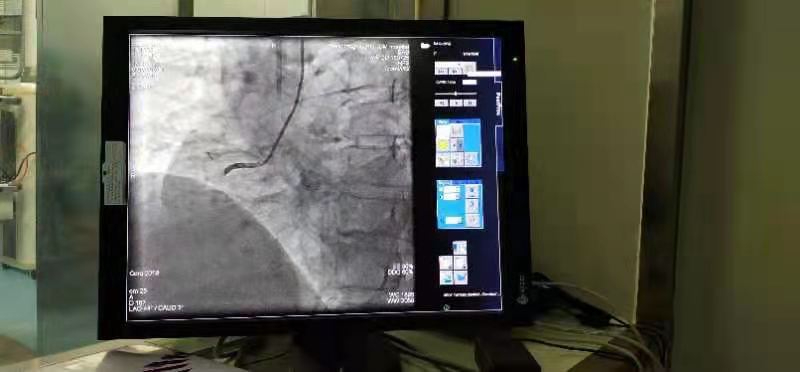

1月14日下午,在鄲城縣第二醫(yī)療健康服務(wù)集團(tuán)鄲城縣中醫(yī)院心病一區(qū)手術(shù)室,經(jīng)過(guò)充分的術(shù)前準(zhǔn)備,集團(tuán)總醫(yī)院副院長(zhǎng)、心病一區(qū)主任楊俊帶領(lǐng)團(tuán)隊(duì),為44歲的冠心病患者朱某男成功實(shí)施了心臟冠脈支架介入治療。與以往手術(shù)不同的是,患者朱某男享受到了國(guó)家集采政策后降價(jià)的冠脈支架,其植入的冠脈支架從原先每枚均價(jià)數(shù)萬(wàn)元降為700元。

手術(shù)的順利完成,也標(biāo)志著首批國(guó)家集中采購(gòu)的醫(yī)用耗材冠脈支架在我院正式落地實(shí)施。

科室主要開(kāi)展冠心病、心肌梗死、高血壓病、心肌病、心力衰竭、心律失常等心血管疾??;2013年與鄭州大學(xué)一附院聯(lián)合首家開(kāi)展冠脈介入支架植入術(shù),填補(bǔ)鄲城縣冠脈介入空白,相繼首家開(kāi)展射頻消融術(shù),并帥先開(kāi)展急性心肌梗死溶栓治療。2018年9月在中國(guó)胸痛中心官網(wǎng)已注冊(cè)申請(qǐng)并全院開(kāi)展胸痛中心建設(shè)。自2013年以來(lái),與鄭州大學(xué)一附院聯(lián)合開(kāi)展冠心病介入治療數(shù)千例,效果顯著,在社會(huì)上享有較高的榮譽(yù)。